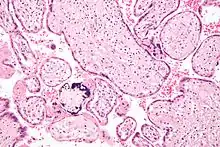

| Micrograph of cytomegalovirus (CMV) infection of the placenta (CMV placentitis), a vertically transmitted infection: The characteristic large nucleus of a CMV-infected cell is seen off-centre at the bottom right of the image, H&E stain. | |